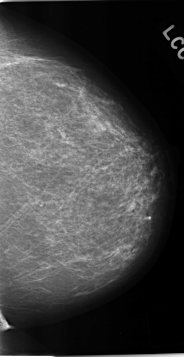

C_0230_1.LEFT_CC

LEFT_CC LINES 4632 PIXELS_PER_LINE 2392 BITS_PER_PIXEL 12 RESOLUTION 50 NON_OVERLAY